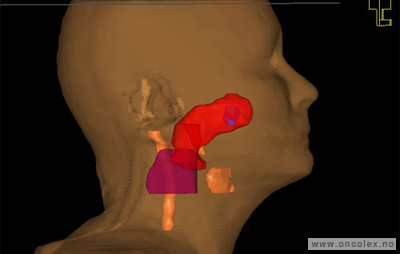

Målvolum

Skisse over hvordan strålefeltet planlegges:

Illustrasjon for målvolum

• GTV (Gross Tumor Volume): Identifisert tumor.

• CTV (Clinical Target Volume) GTV + omkringliggende vev hvor det kan væremikroskopisk spredning.

• ITV (Internal Target Volume): CTV + en indre margin som tar hensyn tilindre bevegelser og endringer av CTV.

• PTV (Planning Target Volume): Innstillingsmargin som inneholder ITV og samtidig tar hensyn til antatte pasientbevegelser, samt variasjoner i pasientopplegging og feltinnstillinger.

• Feltgrense. Tegnes som oftest på kroppen.

ICRU (International Commission on Radiation Units and Measurements)